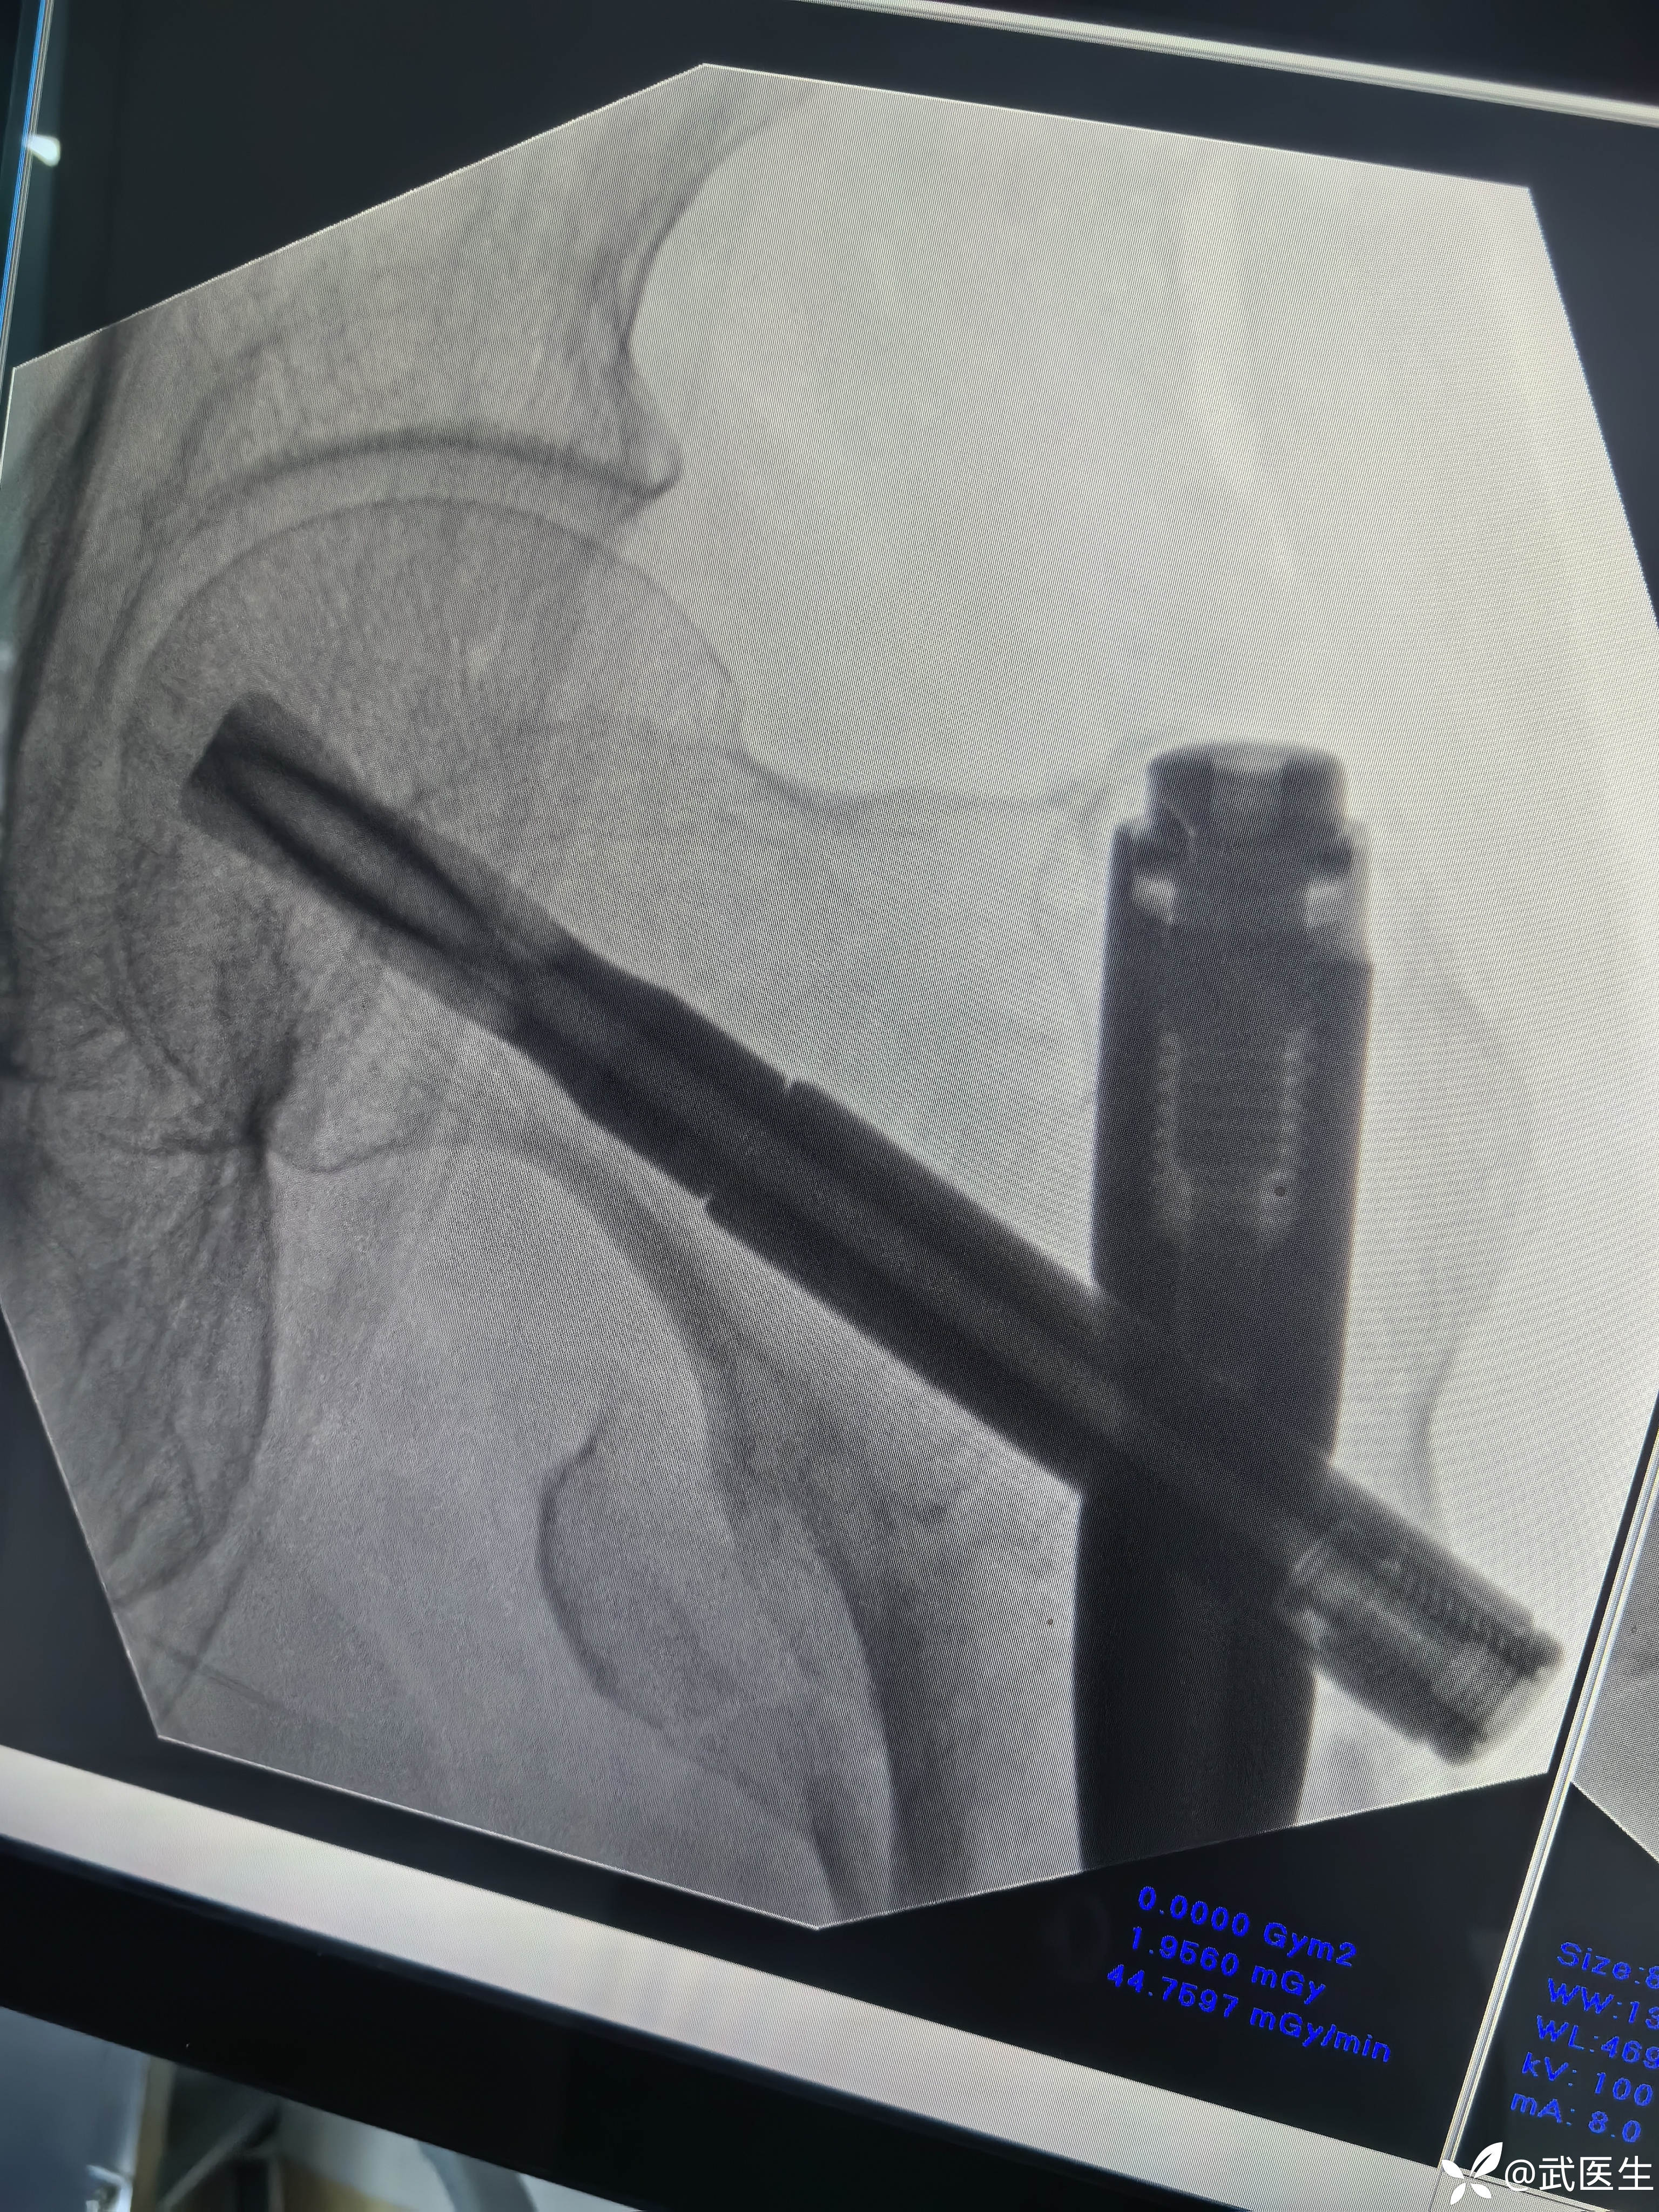

术后常规手术室拍片,如下

正位,骨折对位良好,头颈钉居中偏下,髓内钉顶天立地。

轴位,呦吼,啥情况,后方这个大尖尖……

不处理了,切口如下

如术后侧位图片,各位战友你会返工捆绑钢丝么?